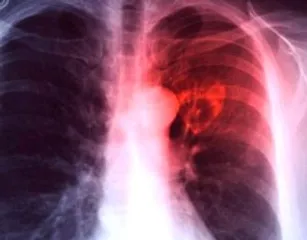

New Delhi: The Centre on Tuesday stated that about 21.69 lakh tuberculosis (TB) cases have been notified between January and October 2024. TB notification has been a concern in India, but the country has seen improvements in recent years.

“Notified TB cases increased from 18.05 lakh in 2020 to 25.52 lakh in 2023,” said Union Minister of State for Health and Family Welfare, Anupriya Patel, in a written reply in the Rajya Sabha. “About 21.69 lakh TB cases have been notified between January and October in 2024,” she added.

“The incidence rate of TB in India has shown a 17.7 per cent decline from 237 per 100,000 population in 2015 to 195 per 100,000 population in 2023. TB deaths have reduced by 21.4 per cent from 28 per lakh population in 2015 to 22 per lakh population in 2023,” Patel said.